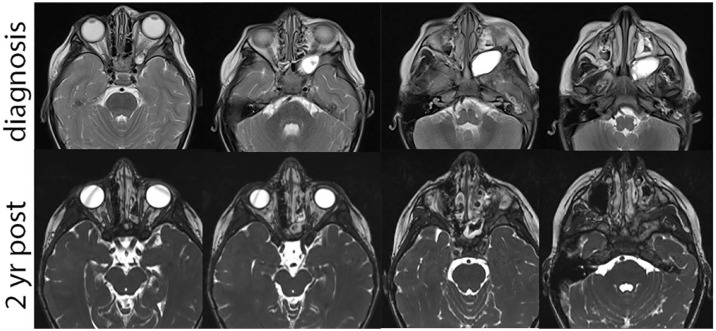

Infratemporal fossa (ITF) tumors are rare in children and may present with a variety of symptoms. Teratomas are neoplasms derived from the 3 germ layers and approximately 6% to 10% are within the head and neck. Our study discusses one of the first reported cases of teratoma in the ITF in a pediatric patient. A 3-year-old girl presents with 2 years of recurrent monthly left periorbital swelling accompanied by fevers, skin discoloration, and pain. Prior episodes were treated with antibiotics with incomplete resolution. Imaging revealed a cystic lesion centered in the ITF. She was taken for endoscopic endonasal biopsy of the lesion and had no complications. Pathology revealed a mature teratoma composed primarily of pancreatic tissue. Providers should consider masses such as teratoma in the differential for ITF tumors and periorbital edema unresponsive to typical treatment.